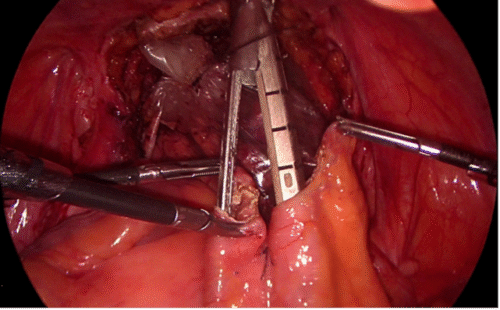

La nefrectomía radical laparoscópica en pacientes con trombo tumoral nivel I y II (T3b) es factible de realizar en manos expertas, manteniendo los principios oncológicos establecidos y la seguridad del paciente(23,24). Inicialmente, se accede por vía transperitoneal al riñón derecho, movilizando el colon y realizando una maniobra de kocher amplia para llegar sin dificultad al hilio renal y a los grandes vasos. Se debe disecar al vena cava por encima y por debajo del hilio renal, especialmente en su cara posterior. De manera habitual, se controlan y seccionan las arterias renales. Posteriormente, con pinzas atraumáticas se evalúa la posición del trombo en la cava. Se introduce una pinza Satinsky laparoscópica y se pinza parcialmente la vena cava, incluyendo el trombo. Esta maniobra evita el sangrado retrógrado por las venas lumbares que se produce al pinzar la cava en sus puntos distal y proximal a la afluencia de la vena renal. Se liga y secciona la vena renal, para tener mayor maniobrabilidad en el manejo de la vena cava. Se completa la disección de la pieza quirúrgica para tener mayor comodidad en la trombectomía. Luego, se efectúa la cavotomía con tijera fría y se extrae trombo. Finalmente, se sutura vena cava con polipropileno 4/0 y se comprueba hermeticidad (Figura 24).

Quienes hemos tenido la experiencia de operar tumores renales con trombos en la cava, hemos sufrido el sangrado que se produce al no tener controladas las venas lumbares. Con trombos hasta nivel II según la clasificación de Novick(25) es posible realizar este procedimiento en forma segura cuando se cuenta con pinzas Satinsky laparoscópicas, disponibles en el mercado. Cuando no se cuenta con estos elementos o el trombo sobrepasa este nivel, es preferible hacer una cirugía abierta.